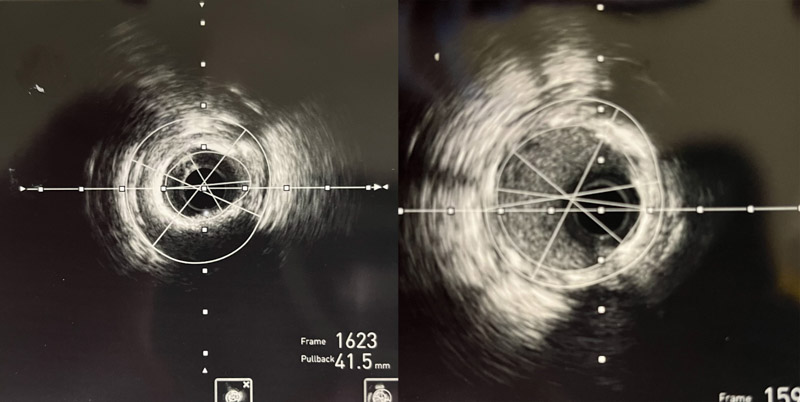

術中,心血管內科介入團隊將Shockwave C2 IVL 3.0*12mm 震波球囊置入前降支病變處,以4-6atm進行擴張后觸發8次10秒沖擊波,實施鈣化斑塊碎裂術,術后支架膨脹不全處明顯擴張,并順利于前降支近中段植入1枚支架。復查IVUS可見鈣化斑塊碎裂,支架貼壁和膨脹良好,血管擴張成形滿意,術后患者胸痛癥狀明顯好轉。

▲震波前、后IVUS對比圖像